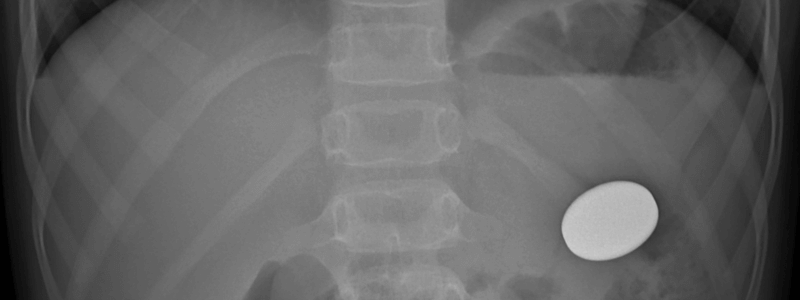

Ingested Foreign Bodies: An Overview

The ingestion of foreign bodies is a common problem that presents frequently to Emergency Departments. Although it can affect any age group, it is most frequently seen in young children between 6 months and 5 years. Coins are the most commonly swallowed objects, but...